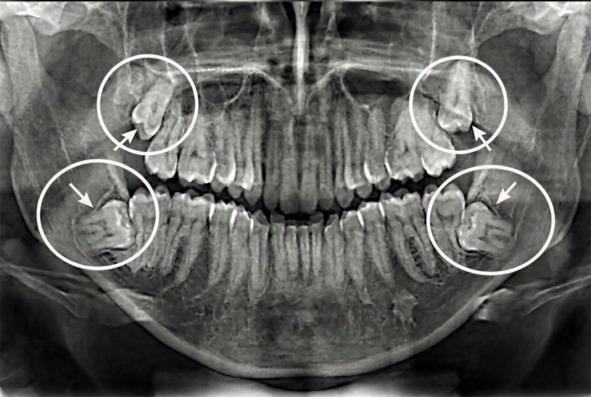

Ретенированные зубы: 1.8, 2.8, 3.8 и 4.8. Джекпот!